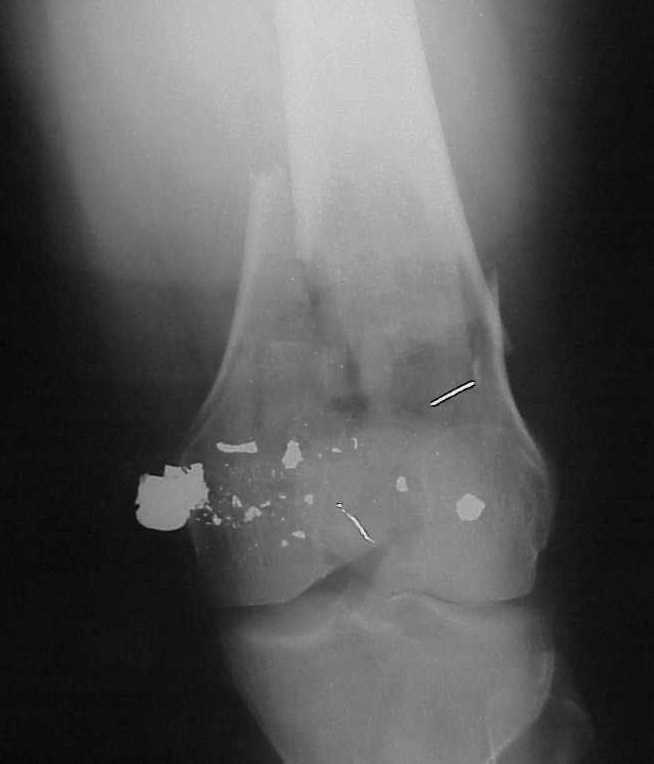

Re: Многооскольчатое бедро

William Obremsky 14 Май 2002, 23:52

See attached case that was done several years ago before LISS. He had comminuted trochlea and anterior blocking screws were used to prevent anterior IMN cut-out.